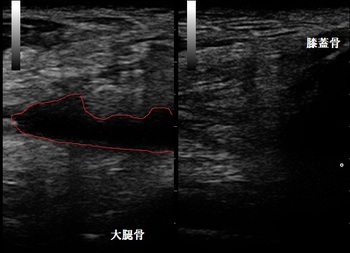

鶴ヶ島市若葉 男性 膝に水が溜った!?膝関節水腫

右膝上部 超音波長軸像 左膝健側

鶴ヶ島市若葉 男性会社員、サッカー少年団コーチ(現監督)。膝に水が溜った!? 膝関節水腫。

8月後半より右ひざの内側が腫れて、お皿の骨(膝蓋骨)が浮いてくるような?違和感を感じるように

当接骨院の来院時は痛みの自己評価は10段階中1とあまり痛みは感じませんでした。膝蓋跳動

(膝関節水腫の徒手検査)は±。超音波検査の結果、右膝蓋上滑液胞に関節液が過剰に貯留している

様子が認められました(左上画像の赤線の囲み)。

【治療】

過剰に溜まった関節液はオーバートレーニングなどの過負担で生じますので、トレーニングの量を

見直します。治療では関節液の吸収を促進させる理学療法、腰から大腿、下腿部の筋緊張を和らげる

マッサージなどを実施していきます。